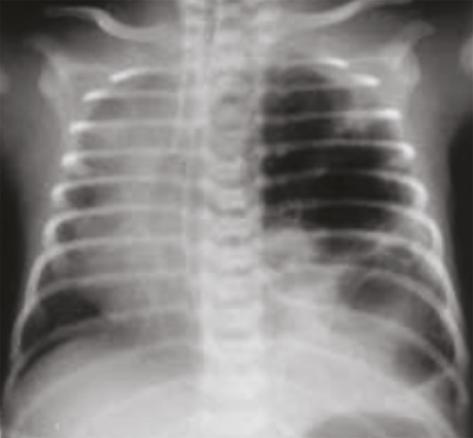

La radiographie pulmonaire objective une hyperclarté avasculaire de l’hémichamp pulmonaire gauche (fig. 1).